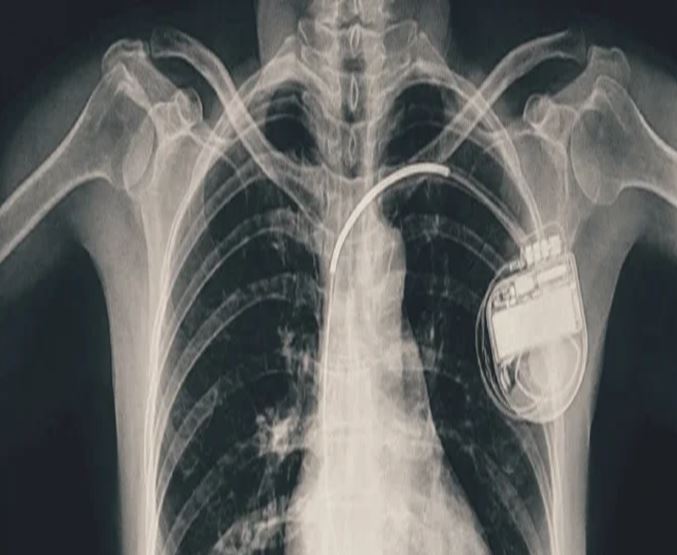

भोपाल। भोपाल मेमोरियल अस्पताल एवं अनुसंधान केंद्र (बीएमएचआरसी) के कार्डियोलॉजी विभाग ने एक दुर्लभ और चुनौतीपूर्ण चिकित्सा उपलब्धि हासिल की है। यहां 13 वर्ष की गैस पीड़ित आश्रित बालिका को इमरजेंसी में डुअल चेंबर पेसमेकर लगाकर उसकी जान बचाई गई। अब बालिका की हालत बेहतर है और उसे अस्पताल से छुट्टी दे दी गई है। यह प्रक्रिया सहायक प्रोफेसर डॉ. अमन चतुर्वेदी और उनकी टीम द्वारा सफलतापूर्वक की गई।

तीन वर्ष की आयु में दिल में था छेद

बीएमएचआरसी के कार्डियोलॉजी विभाग के सहायक प्रोफेसर डॉ. अमन चतुर्वेदी ने बताया कि यह मरीज जन्म से ही हृदय रोग से पीड़ित थी। तीन वर्ष की आयु में उसके दिल में छेद (congenital heart defect) का ऑपरेशन किया गया था। ऑपरेशन के बाद उसे हार्ट ब्लॉक हो गया यानी हृदय की धड़कन असामान्य रूप से धीमी हो गई। इसके कारण उसे चक्कर आना, आंखों के सामने अंधेरा छा जाना जैसी परेशानियां होने लगीं।हार्ट ब्लॉक की स्थिति में, बचपन में ही उसे एपिकार्डियल पेसिंग (epicardial pacing) डिवाइस लगाई गई। इस प्रक्रिया में पेसमेकर के तार हृदय की बाहरी सतह पर लगाए जाते हैं, जो आमतौर पर छोटे बच्चों में अपनाई जाती है, क्योंकि उनके हृदय का आकार छोटा होता है। इस डिवाइस की आयु लगभग 10 वर्ष होती है। डिवाइस की अवधि पूरी होने के बाद हाल ही में मरीज को फिर से वही लक्षण होने लगे। बीएमएचआरसी में जांच के बाद यह स्पष्ट हुआ कि अब उसे एक स्थायी और अधिक उन्नत पेसमेकर की आवश्यकता है। आपातकालीन स्थिति में टीम ने सफलतापूर्वक डुअल चेंबर पेसमेकर प्रत्यारोपित किया। इस जीवनरक्षक प्रक्रिया को अंजाम देने वाली टीम में कार्डियोलॉजी विभाग के सहायक प्रोफेसर डॉ. कपिलकांत त्रिपाठी, डॉ. नुपुर गोयल, मेडिकल ऑफिसर डॉ. अनुराग ठाकुर एवं अन्य सदस्य शामिल थे।

पेसमेकर एक छोटा उपकरण होता है, जो दिल की धड़कन को नियंत्रित करता है। यह दिल को सही गति से धड़कने में मदद करता है। सिंगल चेंबर पेसमेकर हार्ट के सिर्फ एक चेंबर को इलैक्ट्रिक सिग्नल देता है, जबकि डुअल चेंबर पेसमेकर दिल के दो भागों-ऊपरी (एट्रियम) और निचले (वेन्ट्रिकल) चेंबरों को दोनों को सिग्नल भेजता है, जिससे दिल की धड़कन और भी प्राकृतिक तरीके से चलती है। बच्ची के मामले में डुअल चेंबर पेसमेकर इसलिए लगाया गया क्योंकि उसकी स्थिति अधिक जटिल थी और बेहतर तालमेल के लिए दोनों चेंबर तक एकसाथ सिग्नल देना ज़रूरी था।

बीएमएचआरसी के चिकित्सकों का कहना है कि आमतौर पर पेसमेकर अधेड़ उम्र या बुज़ुर्गों को लगाए जाते हैं, लेकिन बच्चों में पेसमेकर लगाने के बहुत कम मामले सामने आते हैं। बच्चों या किशारों में ऐसा करना मुश्किल भी होता है क्योंकि बच्चों का दिल छोटा होता है, जिसमें उपकरण फिट करना कठिन होता है। साथ ही समय के साथ बच्चे का शरीर विकसित होता है, ऐसे में उपकरण का लंबी अवधि तक काम करना तकनीकी चुनौती बन जाता है। यही नहीं, पेसमेकर के तारों की लंबाई, फिटिंग और शरीर के भीतर उनकी स्थिति को भविष्य के हिसाब से बहुत सावधानी से तय करना होता है। बीएमएचआरसी की कार्डियोलॉजी टीम ने सभी सावधानी बरतते हुए मरीज को सुरक्षित रखा।